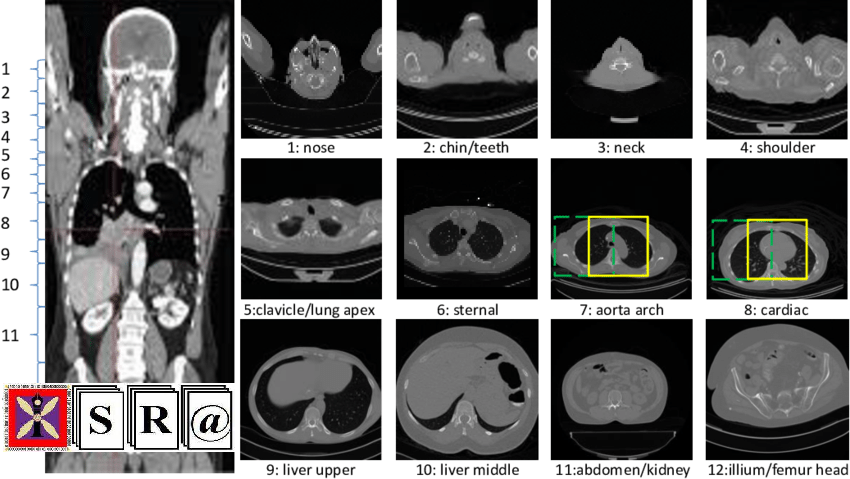

The work ow in CT begins commonly with the acquisition of localizer images, which are also known as scouts or surviews. Such images are acquired prior to the diagnostic scan, with the conventional radiographic projection techniques while the tube is in a stationary position. Typically, the frontal and/or lateral view positions are used. The localizer images play a vital role in optimizing the dose parameters for the subsequent CT scans and in scan planning. The scan plans are generated by the operator for each CT scan by marking a box around the target anatomy, making sure to include all relevant anatomical structures while keeping the box extents minimal.

In contrast to CT images, the localizer images exhibitunnormalized intensities. Also, the overlapping arising from projection results in a lack of differentiation between bodyparts. Such image characteristics pose challenges in their use for image processing applications such as classi[1]cation segmentation. Previous works in this regard include landmark detection in the thorax [1] and annotation of medical radiographs into salient anatomical regions [2]. In [3], a registration-based method was presented for liver slice and navigator position planning using a set of stacked 2D localizer images. Most recently, Saalbach et al. [4] proposed a method for the auto-mated anatomy detection by employing a sequence of classi-[1]ers to [1]rst localize individual anatomies and a probabilistic model to obtain the joint localization of combined anatomies. However, there are several limitations of this method: This approach is limited to obtaining an approximate localization of the anatomies and it can-not generates the segmentation, which could allow dose optimization as well as dose computation for the individual anatomies. Also, in the localization step, the use of Haar basis functions (which have an explicit mathematical formulation) could limit the adaptability of the method. Finally, such a multi-step approach can not be trained in an end-to-end fashion.

In this paper, we investigated a deep learning-based segmentation technique knows as Fovea Convolutional NeuralNetwork (F-Net) [8]. This architecture has been successfully employed for multi-organ segmentation in CT images. As opposed to the use of high-resolution 3D CT images, our method is novel in terms of the use of localizer images for the automatic segmentation of multiple anatomies. Finally, we extended this method for an application to scan planning, as done by Saalbach et al. [4], and compared the two methods. A brief outline of the paper is as follows. In Section 2, we describe the dataset used to train and evaluate our method. We elaborate on the proposed method in Section 3. The results and conclusions are discussed in Sections 4 and 5, respectively.